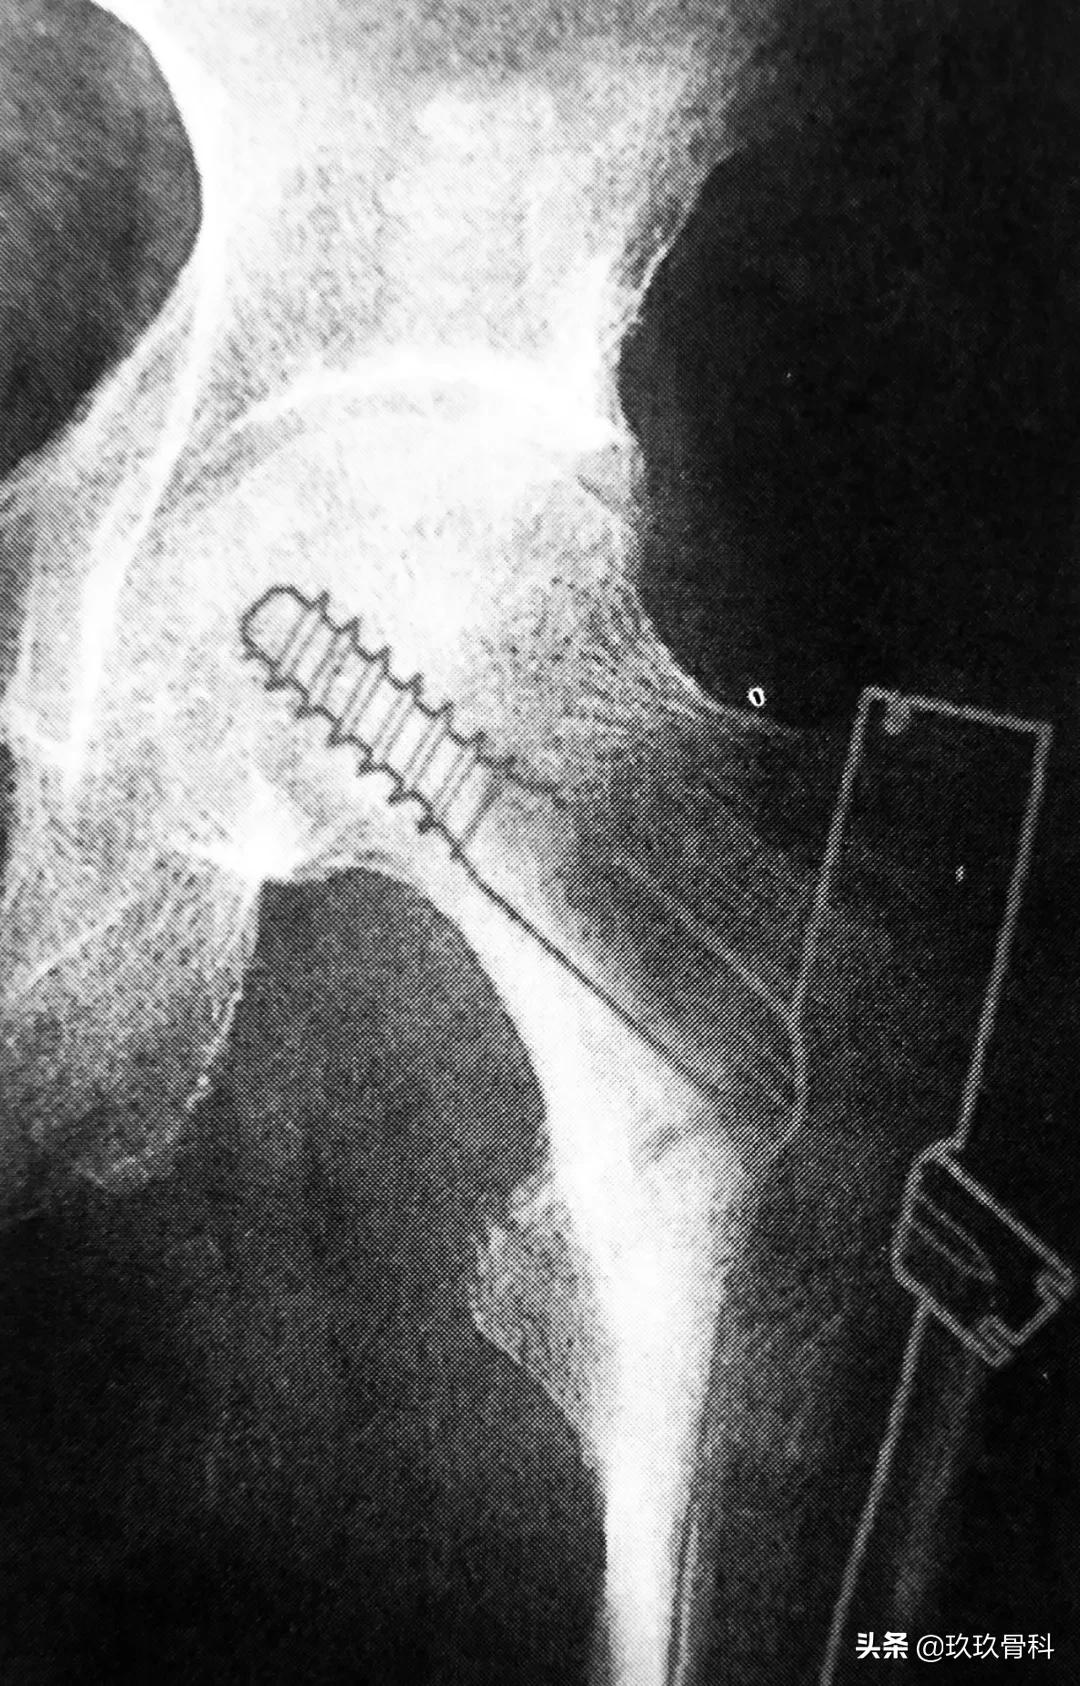

1. Gamma 钉

Gamma 钉适用于股骨颈基底至小转子水平以上的各种类型的骨折。Gamma 钉内固定技术除感染外无绝对禁忌证,伴有严重骨质疏松患者术后的早期活动需要一定的限制。

拉力螺钉的正确放置非常重要,其前提是首先安放好导针的位置,即正位必须与股骨颈轴线重叠或位其稍下方,侧位或斜位导针应在股骨颈中心。

A 拉力螺钉的安装;B 拉力螺钉的正确位置

拉力螺钉的置入,A 确定长度;B 阶梯钻钻孔 C 拧入拉力螺钉并加压